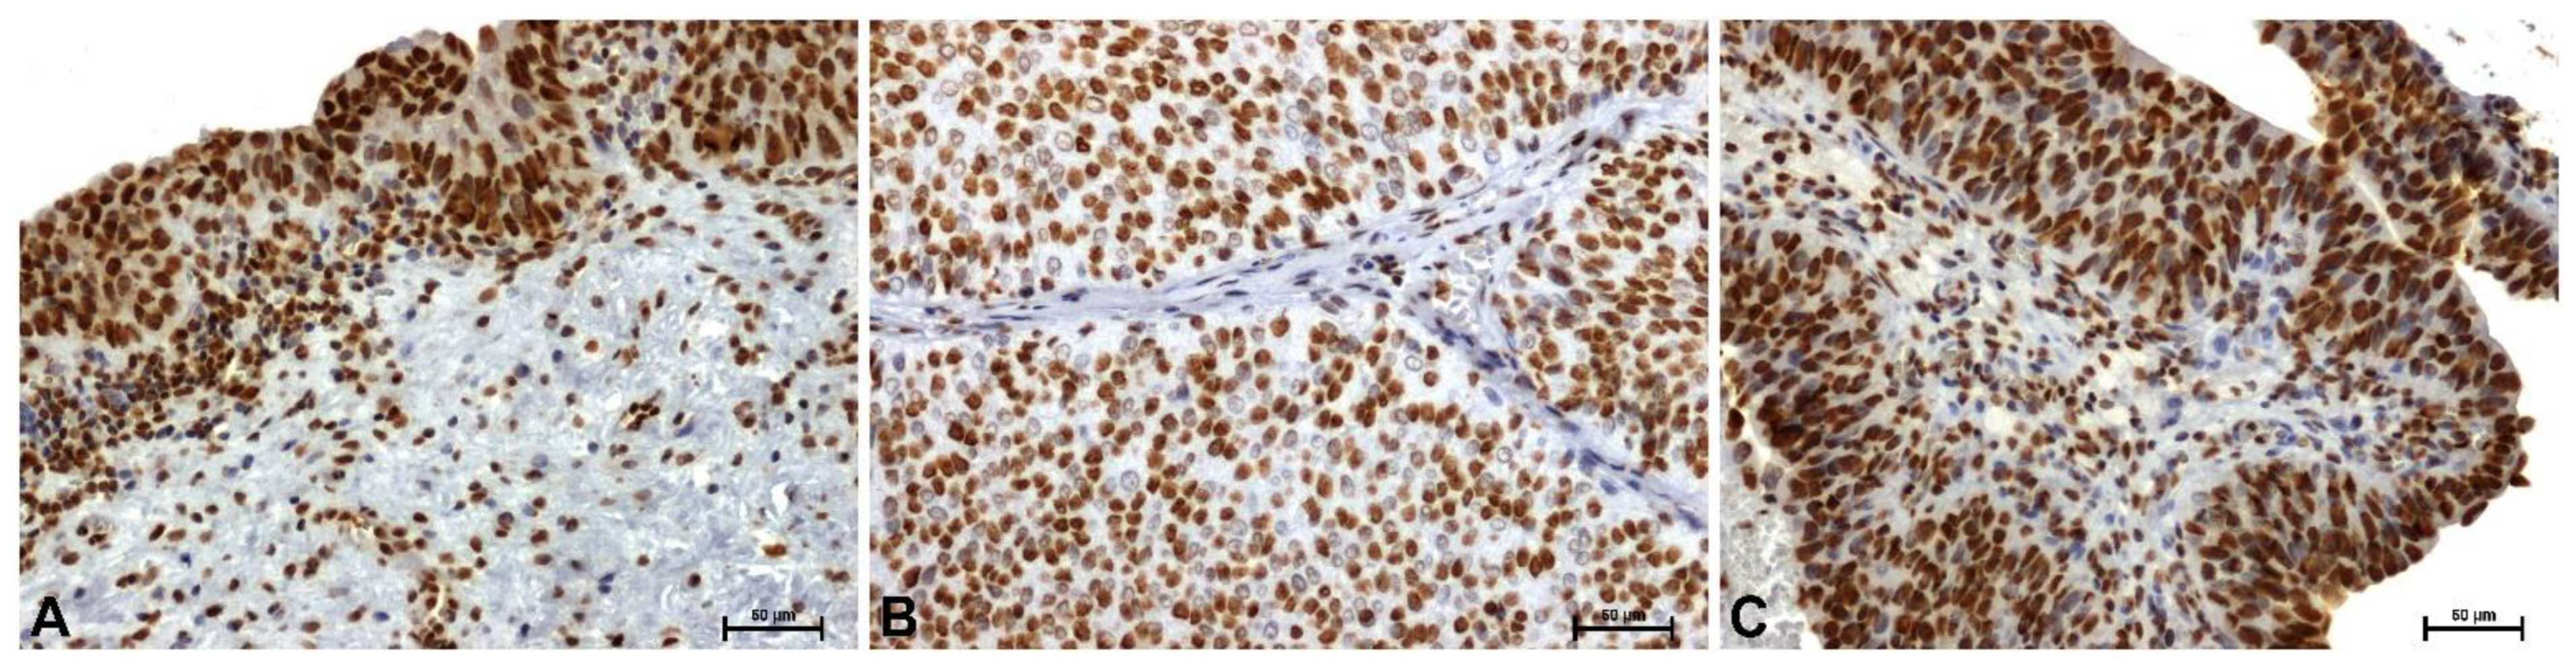

Immunohistochemical Evaluation of HMGB1 in Papillary Urothelial Carcinoma of the Bladder

HMGB1 protein immunoreactivity in control tissues was very strong in the nuclei of epithelial cells and some mucosal cells (Figure 3A). The weakest HMGB1 immunoreactivity was observed in the nuclei of low-grade tumor cells (Figure 3B). High-grade lesions demonstrated strong nuclear immunoreactivity (Figure 3C).

Figure 1. Immunoidentification of HMGA1 in papillary urothelial carcinoma: (A) control, (B) low-grade, and (C) high-grade. Scale bar: 50 μm.